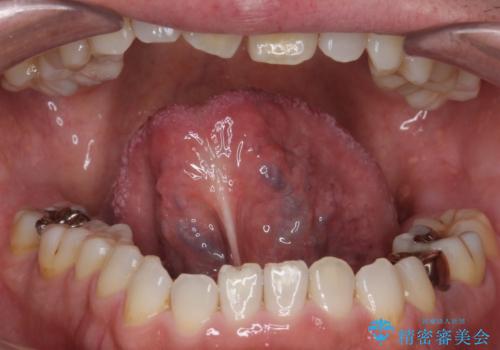

スポーツ用マウスガードを作りたい

- コンタクトスポーツをするためマウスガードを作りたいとのことで来院された患者様です。

色とマウスガードのタイプをお選びいただけます。